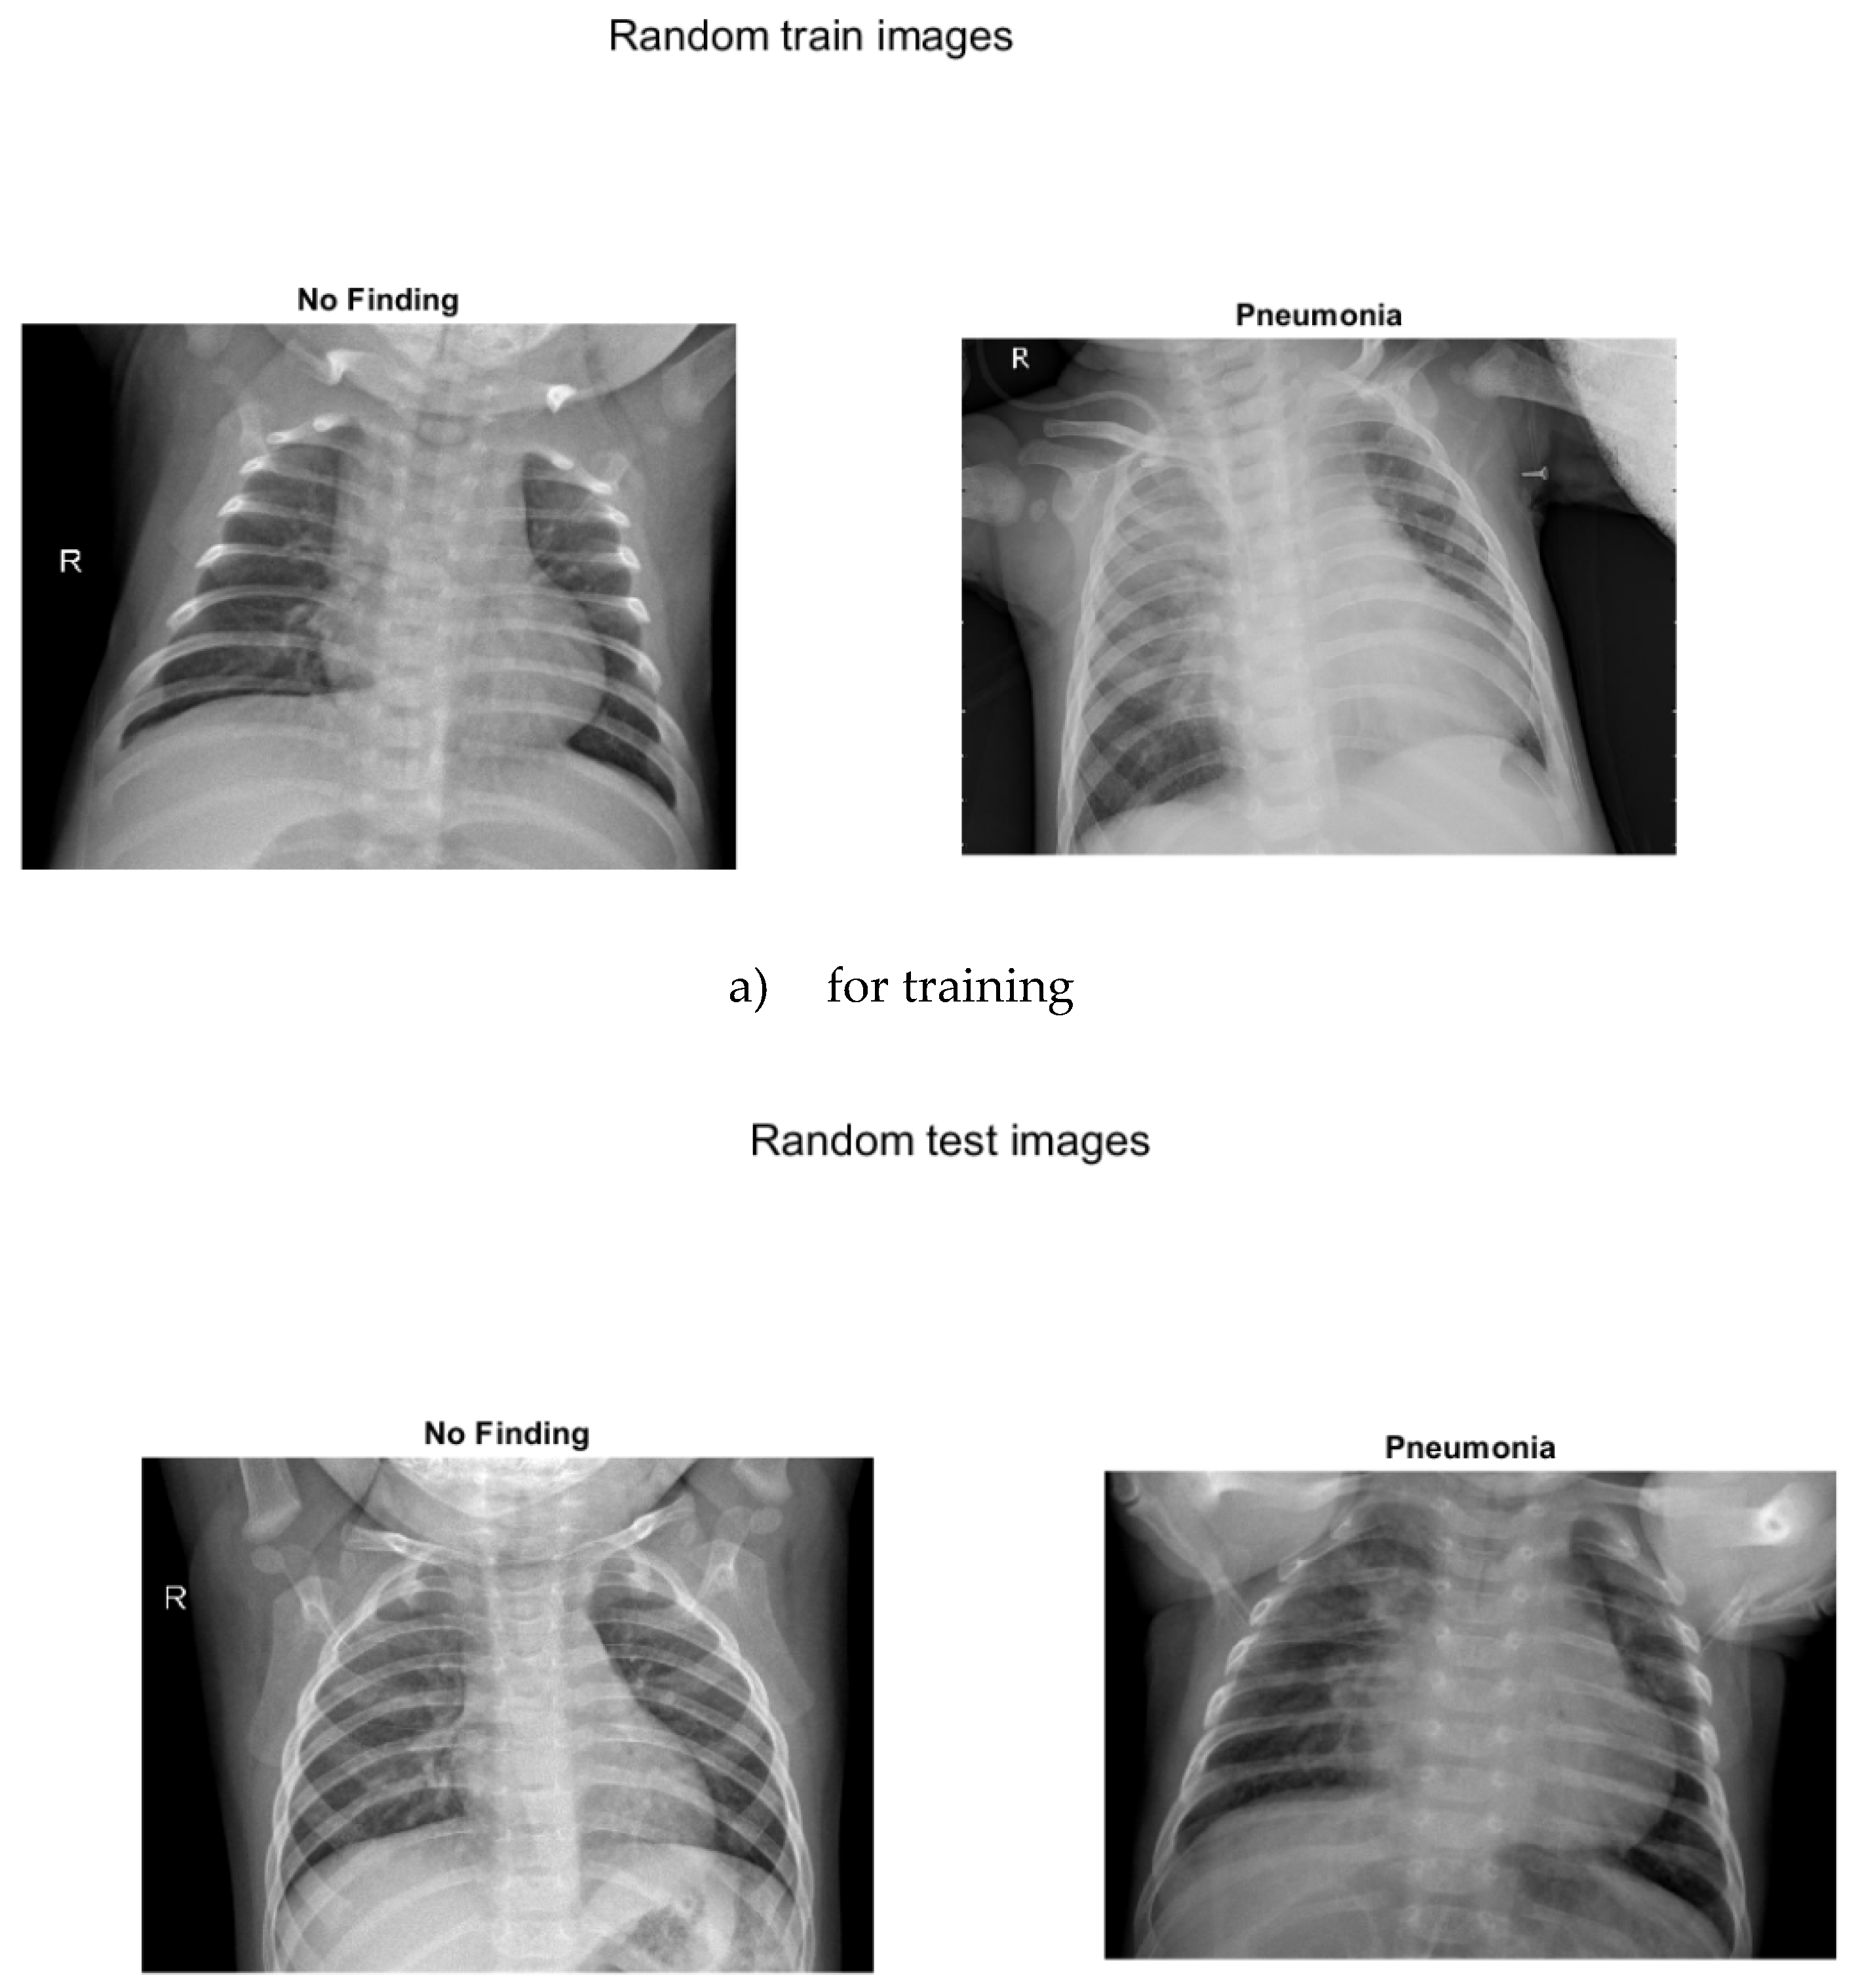

Three separate images show sample images with and without pneumonia of children up to 5 years old

Figure 4. a) for training, b) for testing, c) for verification.